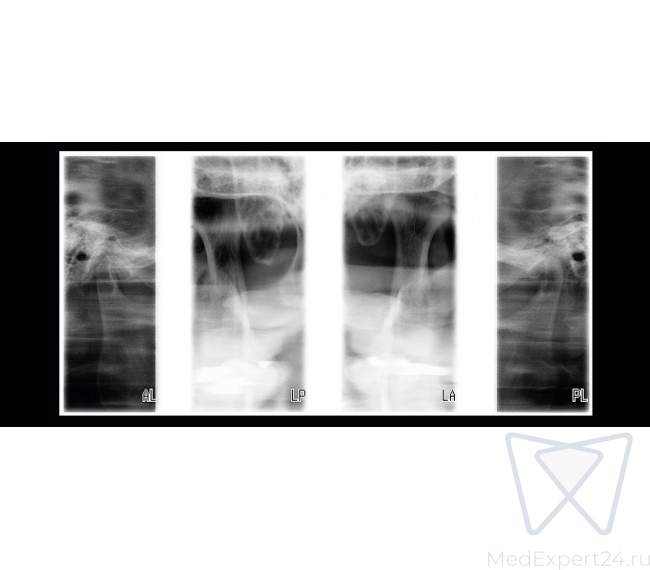

- Задне-передняя двойная ВНЧС программа,